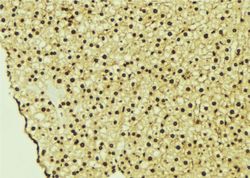

Immunohistochemistry

LS-C809615 IHC